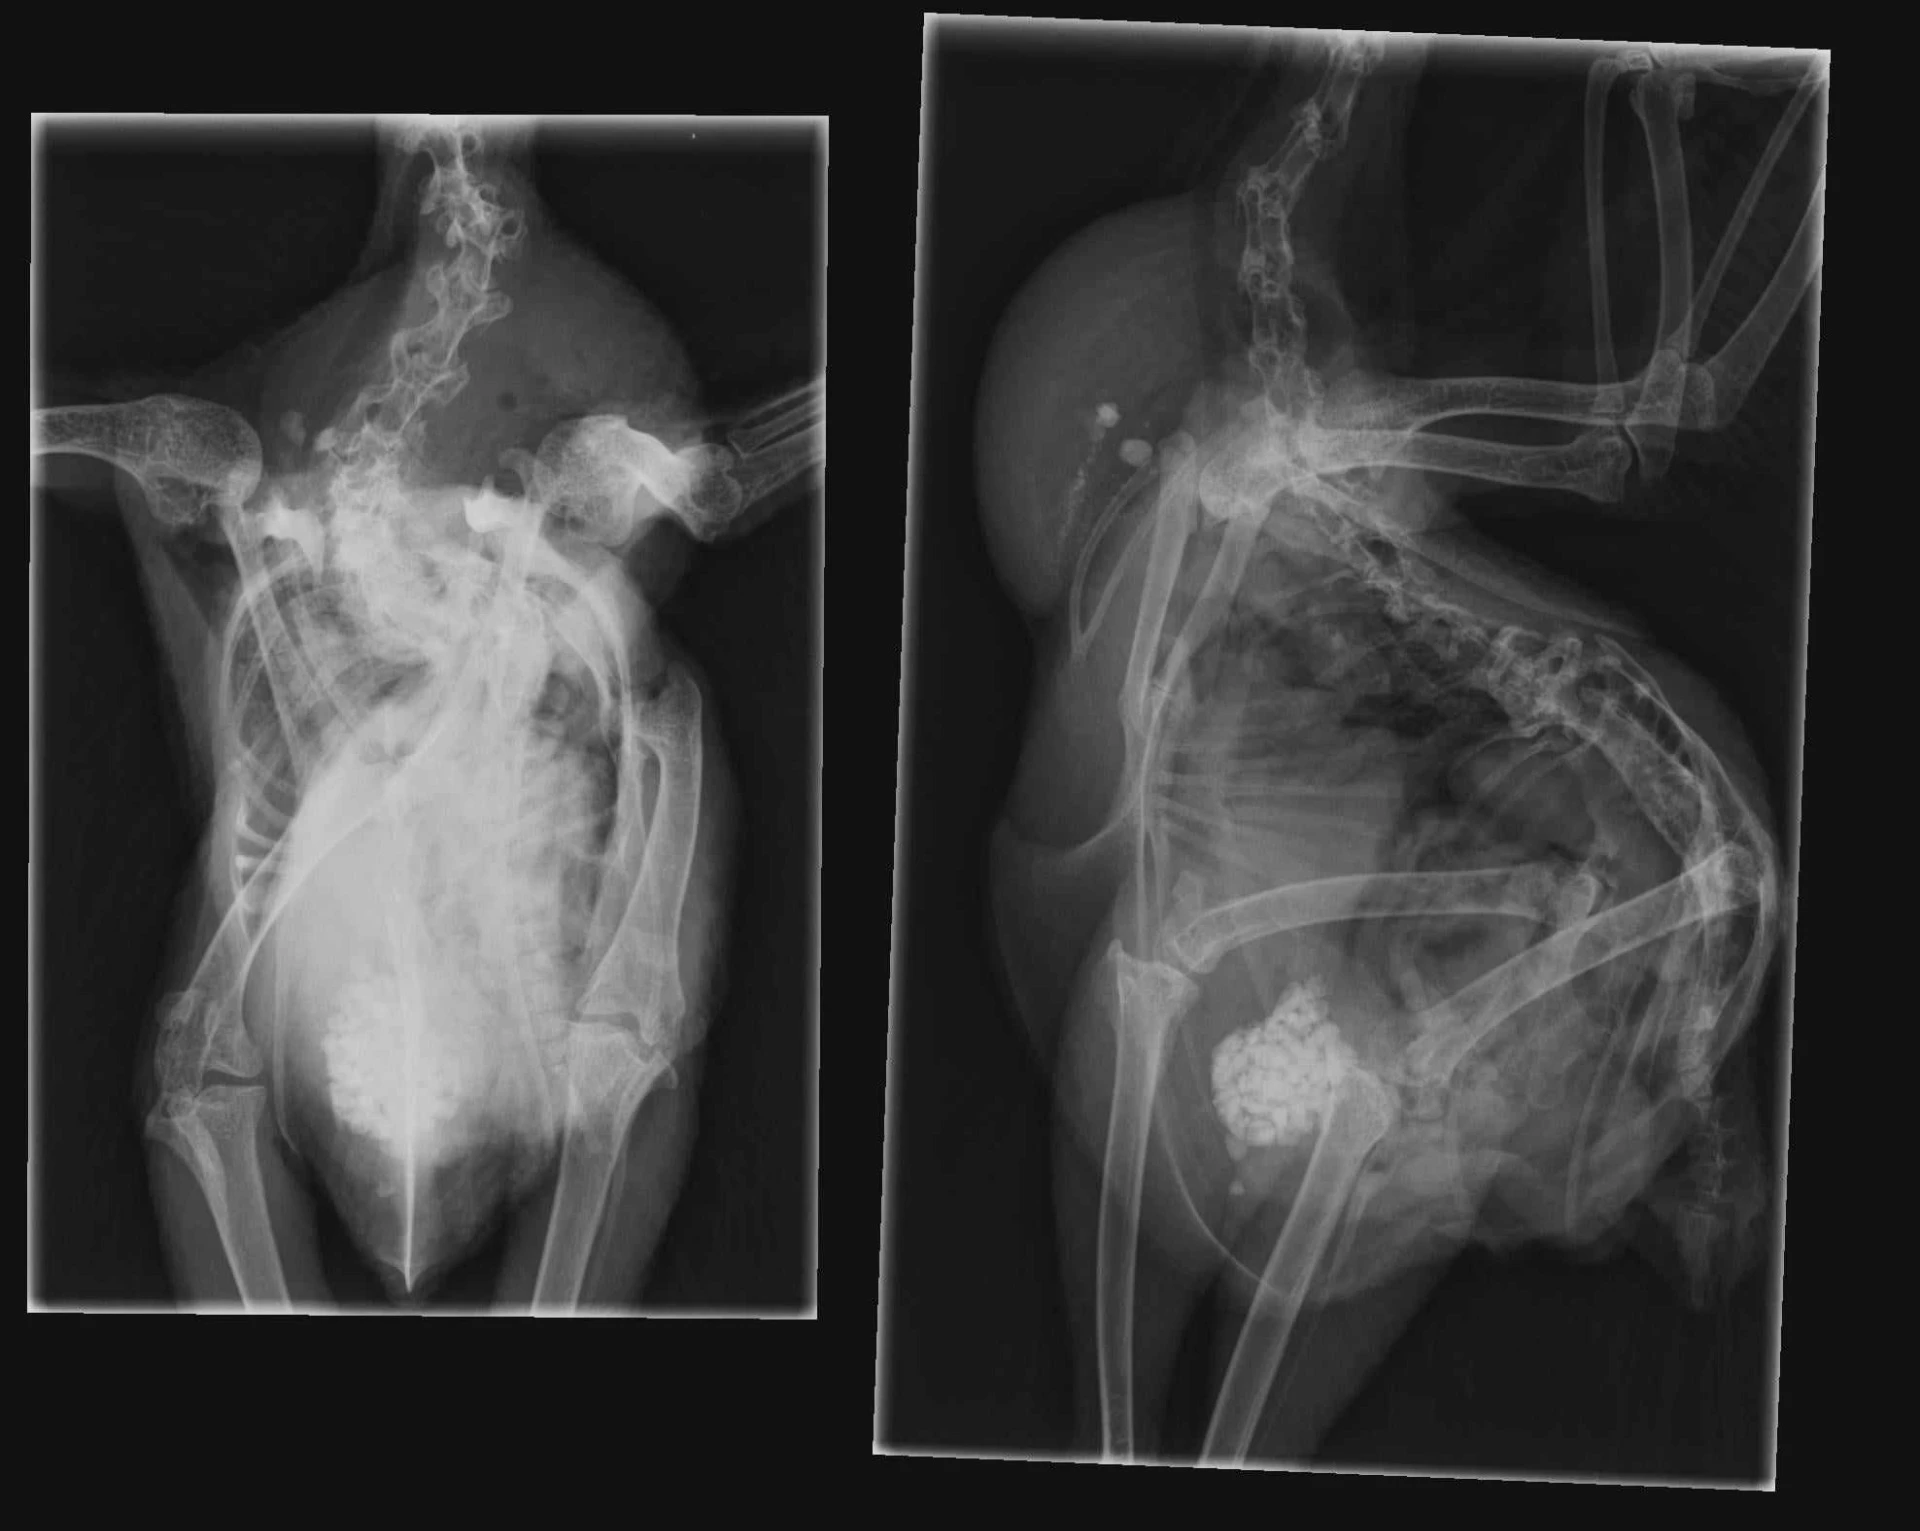

6 mån, Silkestupp

Panic var en silkiehöna med korsnäbb. Han hade en tuff start i livet på grund av korsnäbben, och senare utvecklade han svår skolios. Han var bara hälften så stor som en normal silkiehöna, vilket tydde på att något i hans system inte fungerade som det skulle.

Eftersom han var så liten kunde veterinären inte ens testa honom för aspergillos, han hade inte tillräckligt med blod. Och även om testet hade varit positivt, skulle han inte ha överlevt medicineringen, eftersom hans njurar redan var för svaga för att klara av det.

När jag ser tillbaka och gjorde research för denna artikel är jag ganska säker på att Panic hade den kroniska formen av aspergillos och redan var infekterad när han kom hit.

Det fläckiga på röntgen bilden tyder på Aspergillios infektion, kan ni även se den grava Skoliosen